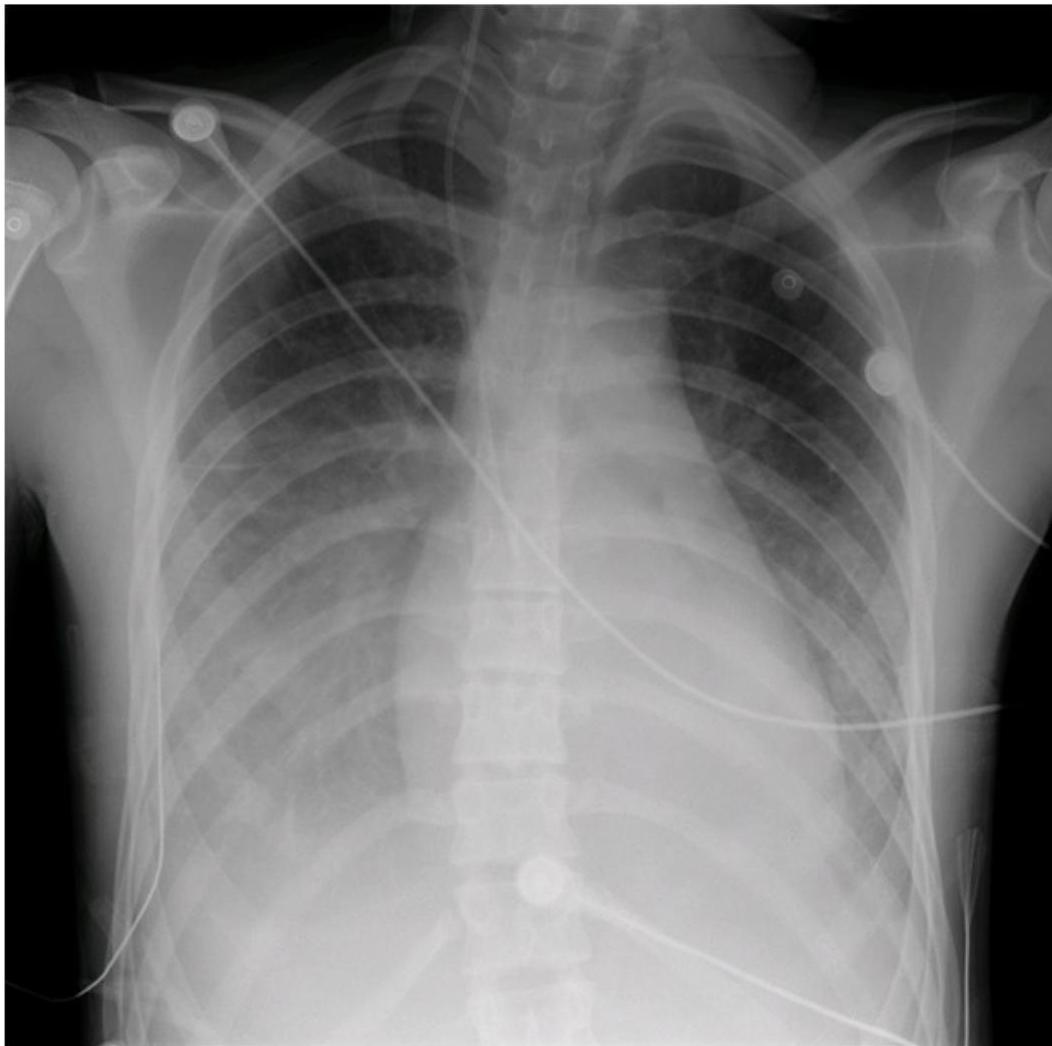

Chest radiograph of an adolescent with viral myocarditis img-8.jpeg Mild cardiomegaly, bilateral pleural effusions, prominence of central pulmonary vessels, interstitial haziness, suggestive of pulmonary edema. Child was a previously healthy 15-year-old boy who presented with severe chest pain in the setting of a viral prodrome.